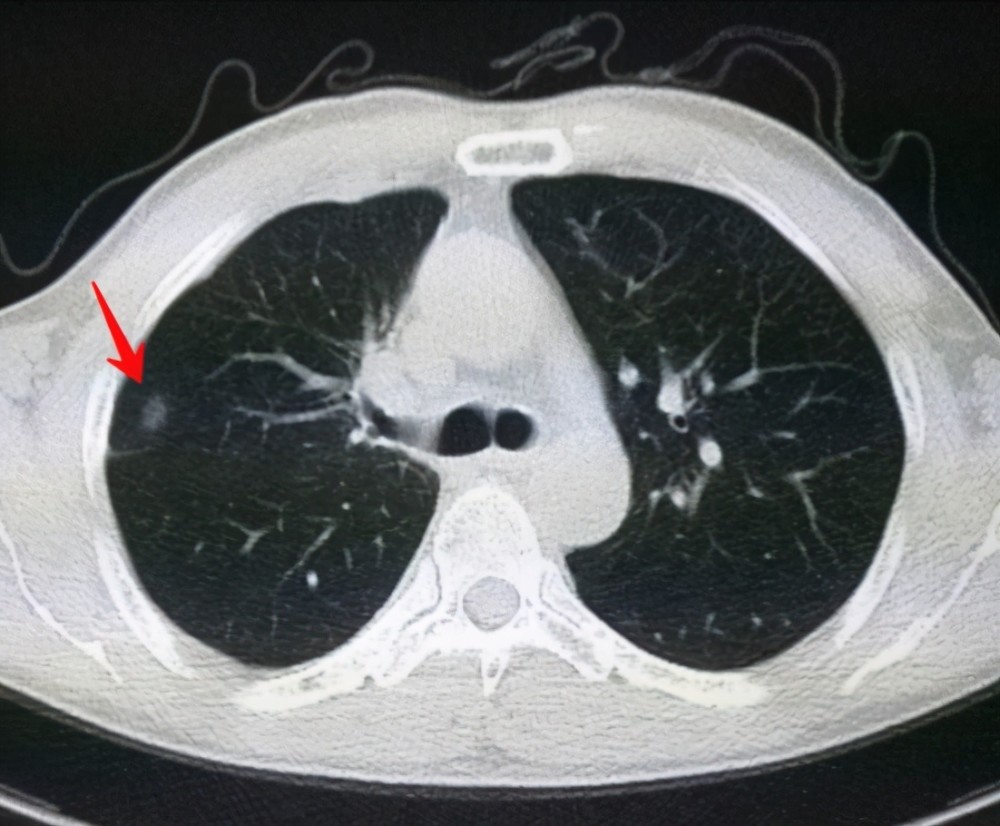

肺結節是一種常見的肺部疾病,其發病率逐年上升,雖然肺結節多數情況下是良性的,但也有可能惡化為肺癌,了解肺結節的形成原因對于預防和治療具有重要意義,本文將為您詳細解析肺結節的形成機制。

肺結節的形成原因

1、環境因素

環境因素是肺結節形成的重要原因之一,長期暴露于污染環境中,如空氣污染、化學污染等,可能導致肺部吸入有害物質,從而引發肺結節,長期接觸石棉、硅塵等職業環境因素也可能增加肺結節的發病風險。